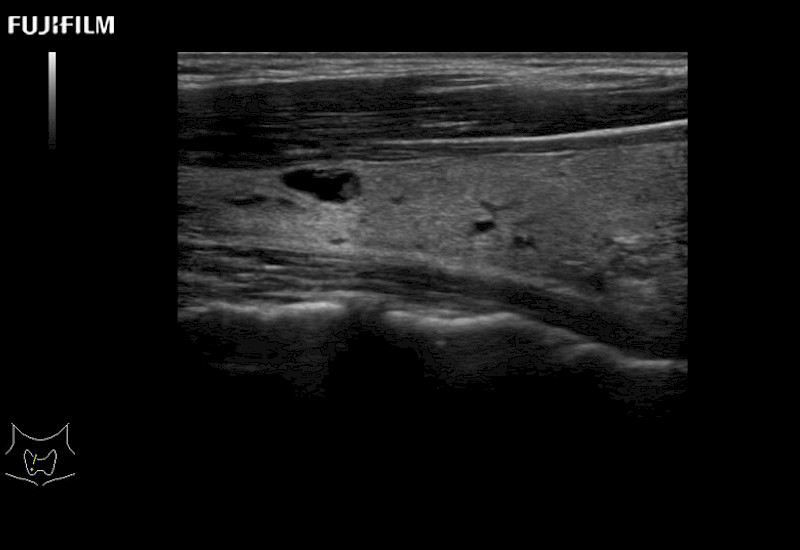

Learn moreFujifilm Healthcare continues to listen to the experts, our neurosurgeons, by developing an ultrasound system specifically designed for the Operating Room.

Guidance is the fundamental purpose for all of our surgical ultrasound technology. Fujifilm Healthcare is committed to designing tools that help neurosurgeons navigate inside the human body and provide the necessary information to immediately make critical surgical decisions.

With the ARIETTA Precision the next level of surgical ultrasound is here.